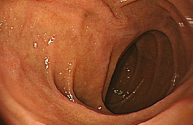

정상 위의 내시경 사진